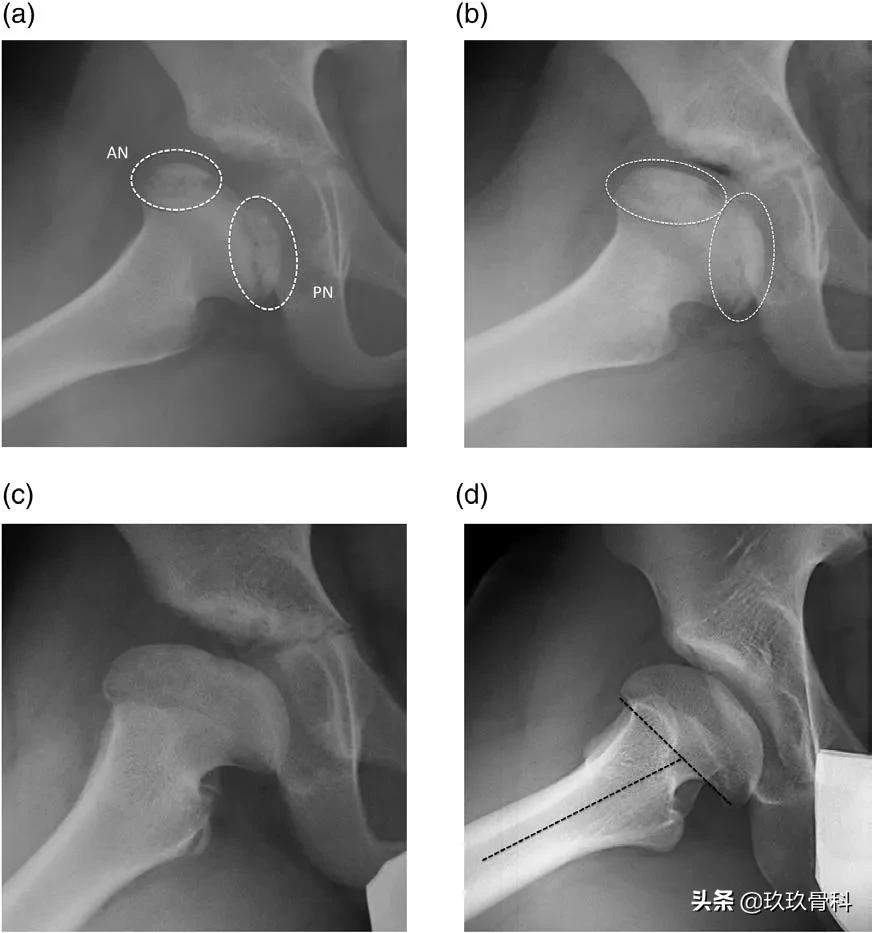

图3. 侧位X线检查显示椭圆形过程。(a)在骨化阶段开始的那一年进行X线检查。观察到两个独立的二次骨化中心,以及骨骺的主要角度。(b)前方X线检查。在前方骨骺二次骨化中心的底部观察到前半骨骺狭窄。后方骨骺二次骨化中心下方的后半骨骺是开放的。(c)2年时对前方进行X线检查。前半骨骺与干骺端完全融合,而后方骨骺二次骨化中心继续具有可见的骨骺。两个骨骺二次骨化中心之间的中央区域仍未骨化。(d)最终的Stulberg IV期结局,伴有髋外翻、股骨头中央扁平和股骨头倾斜,且骨干-骨骺角增加。